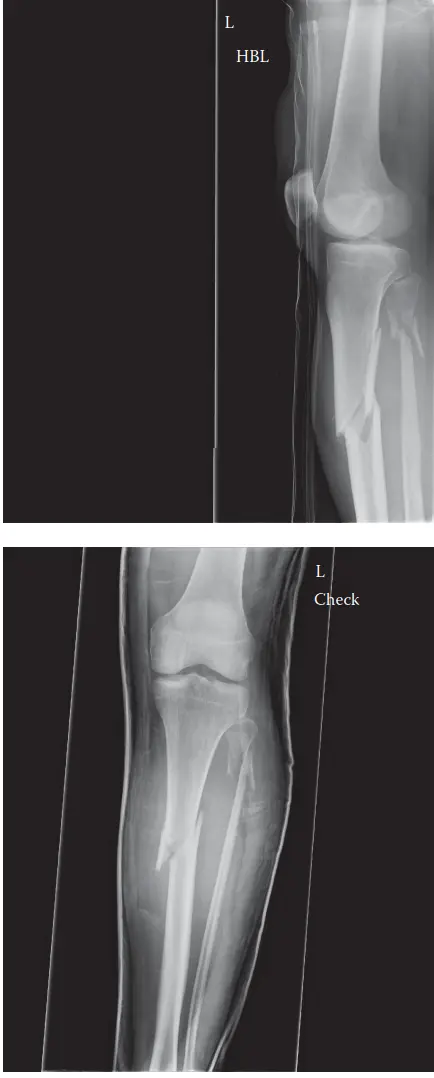

التصوير بالأشعة السينية

تُعد الأشعة السينية (X-rays) هي الخطوة التشخيصية الأولى والأكثر شيوعًا. يتم الحصول على صور بالأشعة السينية للساق المصابة من زوايا مختلفة (أمامية خلفية وجانبية)، ويجب أن تشمل الصورة كامل عظمة الساق، من مفصل الركبة إلى مفصل الكاحل، لتقييم الكسر بالكامل والبحث عن أي إصابات مرافقة.

صورة بالأشعة السينية لكسر معقد في عظمة الساق القريبة

ما تُظهره الأشعة السينية:

* موقع الكسر: تحديد ما إذا كان الكسر في الثلث القريب من جسم عظمة الساق.

* نمط الكسر: هل هو كسر مائل، عرضي، حلزوني، أو مفتت (متعدد الشظايا)؟

* الإزاحة والزاوية: مدى تحرك أجزاء العظم المكسورة عن مكانها الطبيعي، ووجود أي انحناء أو زاوية غير طبيعية.

* تقصير العظم: مدى وجود تقصير في طول الساق.

* كسر الشظية المصاحب: غالبًا ما يظهر كسر في عظمة الشظية في نفس مستوى كسر القصبة.

* استبعاد الامتداد داخل المفصل: تُظهر الأشعة السينية ما إذا كان الكسر يمتد إلى مفصل الركبة أو الكاحل، على الرغم من أن التصوير المقطعي المحوسب يكون أكثر دقة في هذا الصدد.